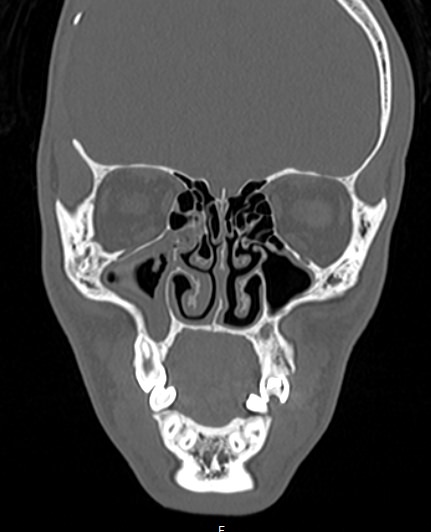

Лицевой череп состоит из крупных костей (верхняя и нижняя челюсти, лобные кости, скуловые кости) и сгруппированных вокруг них остальных мелких костей. При травмах лицевых костей часто наблюдается смещение мелких отломков, которые не видны при обычной рентгенографии. Мультиспиральная компьютерная томография позволяет детально изучить кости лицевого черепа, а также углубления, которые являются вместилищем для важных органов (глазницы, полость носа, ротовая полость).

Метод КТ основан на применении рентгеновского излучения и различной способности тканей поглощать рентгеновские лучи. Костные структуры обладают наибольшей плотностью по сравнению с другими тканями, поэтому в большей степени поглощают рентгеновские лучи и лучше всего визуализируются при данном исследовании.

КТ костей лица является наиболее информативным методом диагностики травм лицевого черепа, посттравматических деформаций, аномалий развития, инородных предметов в носовой полости и околоносовых пазухах. Кроме того, мультиспиральная КТ применяется при воспалительных заболеваниях ЛОР-органов, а также для выявления опухолевых образований доброкачественного и злокачественного характера.

Детальные изображения костей лицевого черепа получаются за счет вращения трубки томографа с излучателями рентгеновских лучей вокруг объекта исследования. В аппаратах увеличено количество сверхчувствительных детекторов, позволяющих производить множество послойных снимков с толщиной среза от 0,5 мм, которые затем преобразуются в трехмерные пространственные модели черепа. Такие инновационные возможности аппаратов обеспечивают проведение точной и достоверной диагностики.